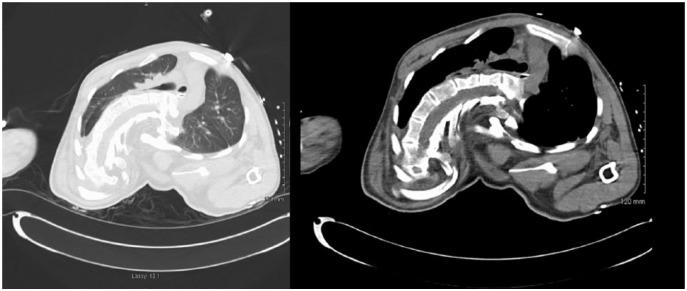

Coffin-Lowry syndrome is expressed as different phenotypes in males and females. In males, it is characterized by facial abnormalities, marked developmental disability, and skeletal changes. Approximately 80% of cases are associated with kyphoscoliosis, which can be quite severe, as seen in our patient, causing paraplegia and restrictive lung disease. In this article, we present the third oldest documented male case of Coffin-Lowry syndrome with severe kyphoscoliosis, paraplegia, and restrictive lung disease.